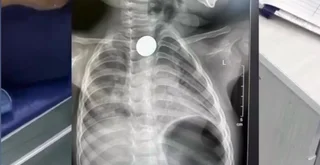

Бишкекте наристенин кызыл өңгөчүнө тыгылып калган тыйын операциясыз чыгарылды